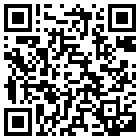

重度の虫歯(根尖性歯周炎)

重度の虫歯になると、歯の根元あたりの歯茎が膨らみ、膿が出てくるようになることがあります。虫歯が進み、神経まで達すると、はじめは「歯髄炎」という状態になり、強い痛みを引き起こします。

さらに、感染が進行して神経が死んでしまうと、細菌が根の奥まで入り込み、根尖性歯周炎(こんせんせいししゅうえん)と呼ばれる状態になります。

これは歯の内部で細菌が繁殖し、根っこの先に炎症が起きている状態です。

感染が進行すると、根っこの先に膿がたまってきます。膿が広がると骨を溶かし、歯ぐきに出口(瘻孔〔ろうこう〕)を作ることがあります。瘻孔は歯ぐきに小さなにきびのようなふくらみとして現れ、そこから膿が出てくるようになります。

歯根嚢胞(しこんのうほう)になると、歯ぐきから膿が出るようになることがあります。根尖性歯周炎が長期間放置され慢性化すると、根の先にたまった膿が膜で覆われ、丸い袋状に形成されます。

このように、歯の根の先端に膿や液体がたまった袋ができた状態を歯根嚢胞(しこんのうほう)と呼びます。

歯根嚢胞は、まだ一度も根管治療を受けたことがない歯でも、すでに根管治療を受けた歯でも起こり得ます。つまりどちらの場合でも根尖性歯周炎の状態が慢性的に続くと、歯根嚢胞に発展する可能性があるのです。

初期の段階では、ほとんど症状がないままゆっくりと進行していきます。ですが、袋の中の内容物や膿が増えると、周囲の骨を溶かし、歯ぐきに出口(瘻孔〔ろうこう〕)をつくって膿が出てくることがあります。他にも、歯根嚢胞が進行すると以下のような症状が出てくることがあります。